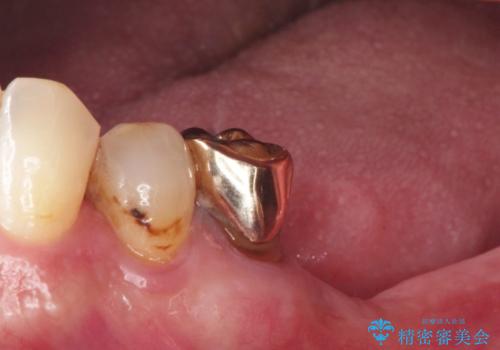

【インプラント】銀歯が取れて歯ごと折れた

- 「奥歯の銀歯が取れた」を主訴に来院された患者さんです。

診査診断を行った結果、歯が折れた位置が深く、虫歯にもなっていたため抜歯後、インプラントで治療を行いました。

残根状態の歯を抜歯後、抜歯窩の治癒を待ちインプラントを埋入しています。